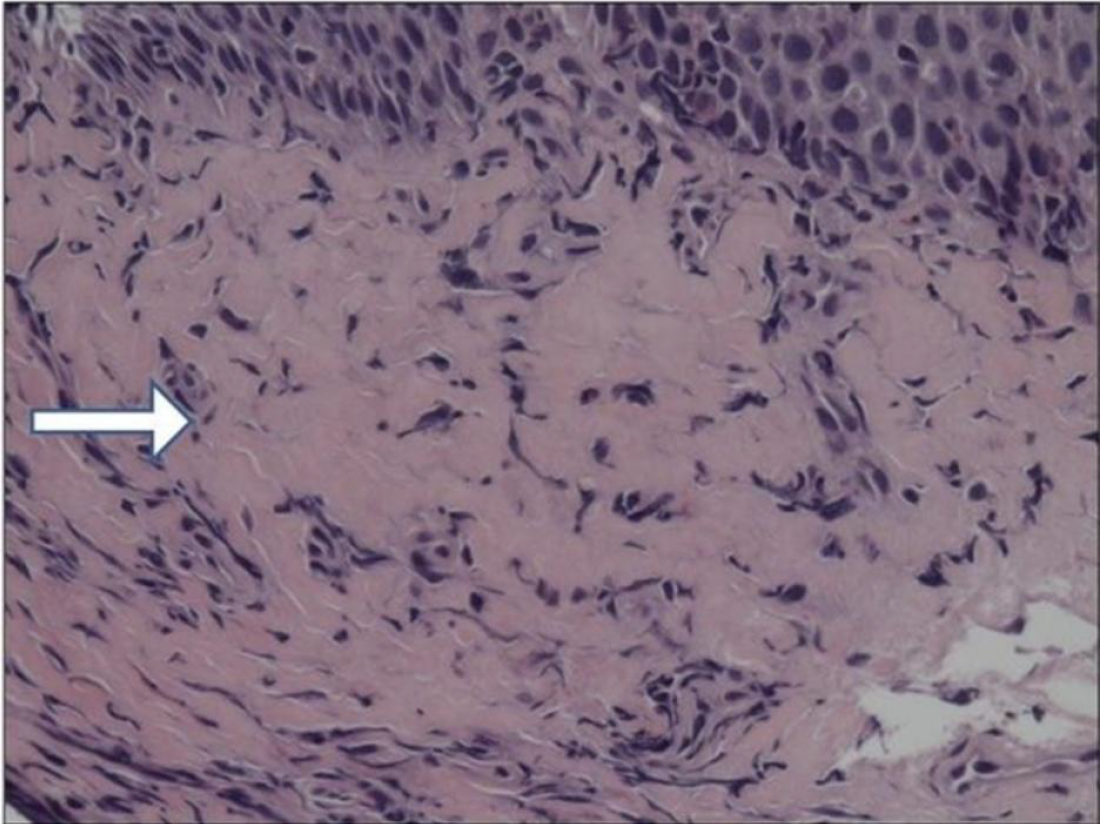

Figure 3 Esophageal epithelium in long-standing eosinophilic esophagitis.

Microphotograph shows a marked increase of fibrotic tissue in the subepithelial layer (white arrow)[22]. Citation: Straumann A, Schoepfer A. Update on basic and clinical aspects of eosinophilic oesophagitis. Gut 2014; 63: 1355-1363. Copyright© The Authors 2026. Published by BMJ Publishing Group. The authors have obtained the permission (Supplementary material).